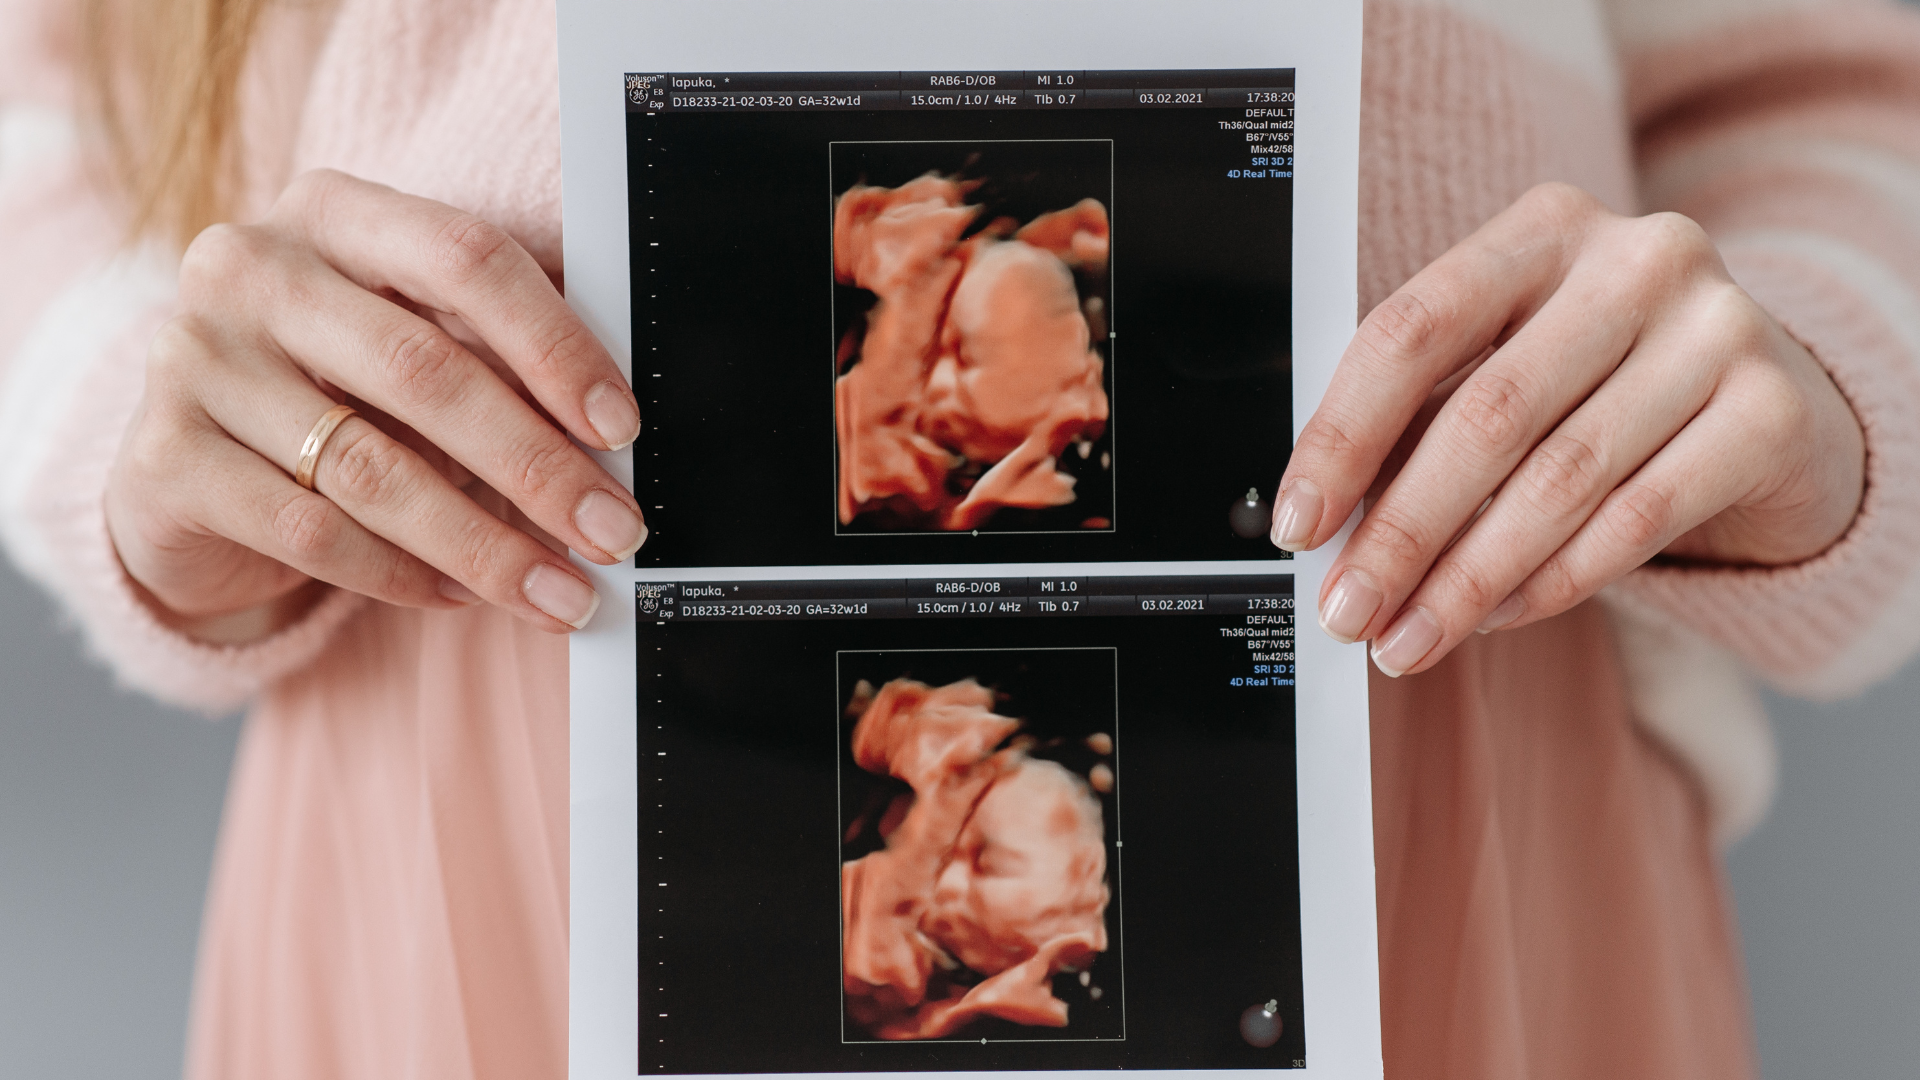

Siêu âm 2D, 3D, 4D khác nhau thế nào trong phát hiện hở hàm ếch?

- Siêu âm 3D: Tái tạo hình ảnh không gian của khuôn mặt thai nhi, giúp quan sát rõ hơn vùng môi - mũi - hàm;